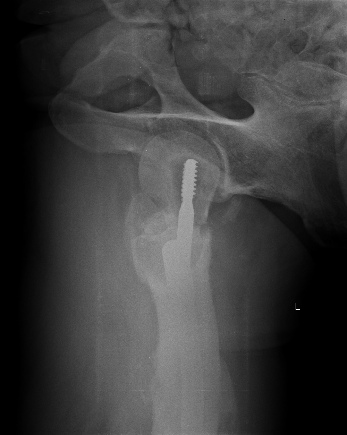

Насчет ревизионного штифтования - вот пример, вчера сделали.

Имя     : 1a.jpg

Тип     : image/jpeg

Размер  : 45468 байтов

Url     : http://weborto.net:8080/pipermail/ortho/attachments/20130531/0a9354ad/attachment-0005.jpg